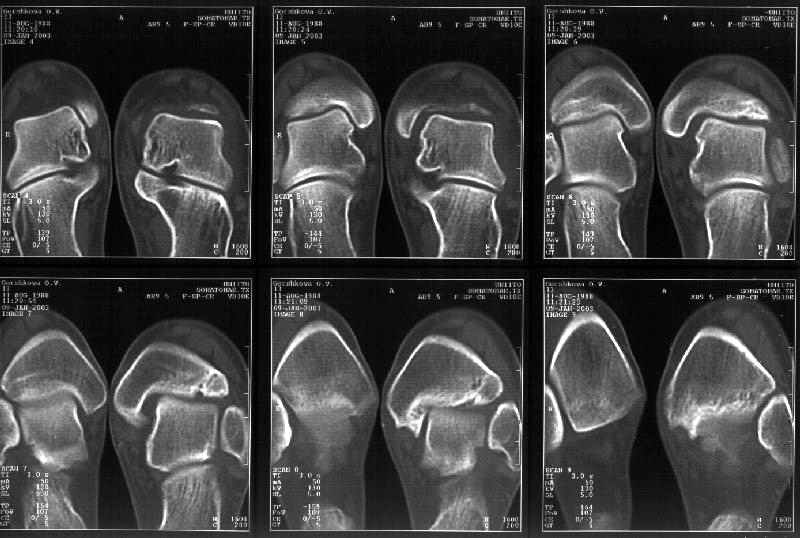

Отправитель: Й. Воск 19 Январь 2003, 22:29

Я пометил линию перелома черной линией.

К сожалению на последних присланных срезах КТ нет более низкого, через таран, среза, который был на прежнем майле. На XR я попытался показать

стержень внутри сустава и то как он раскрывает пространство между тараном и мед. малеолом.

Сегодня пациентке сделали сравнительную КТ. А ксиальные и Фронтальные срезы приложены. Ваше мнение?

Фронтальные

Аксиальные

На КТ я попытался изобразить скромными своими способностями (А)- место перелома, (С)- нормальный суставной зазор меж тараном и тремя его маллеолами. (В)- образовавшийся в результате перелома широкий раза в три зазор, позволяющий, по-моему, сублюксацию тарана при ходьбе. В свете данных КТ, критически важных, я бы предложил вертикальную остеотомию места перелома

задне-внутренним подходом и фиксацию мед. маллеола прижатым к тарану с помощью тонкого compression screw. После этого гипсовый сапожок и немедленное расхаживание ноги.